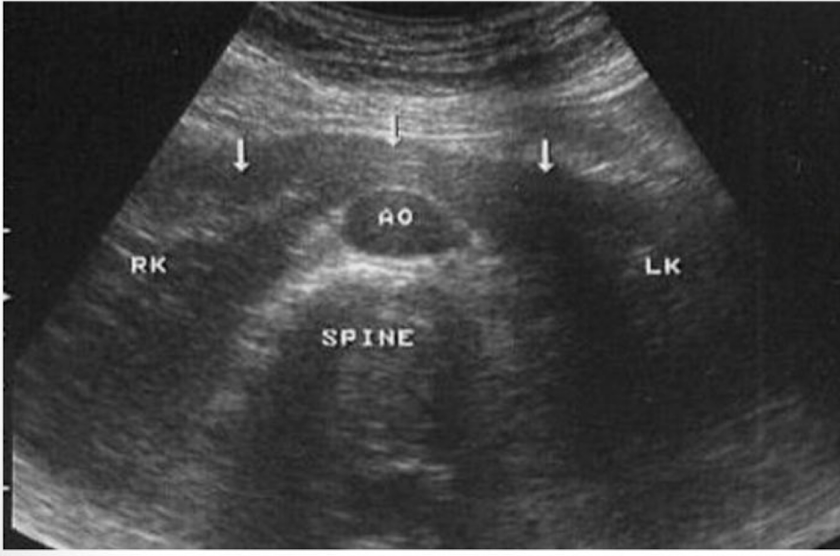

Which type of kidney image is this?

longtudinal